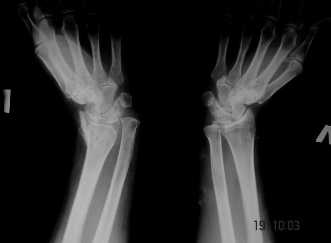

Обратилась женщина, 55 лет. Травма 3 месяца назад, лечилась по месту жительства (Рис.1). Косорукость, боли, ограничение движений. Досняли - рис.2-6. Хотелось-бы услышать мнения  об объеме операции.

Имя     : 1.JPG